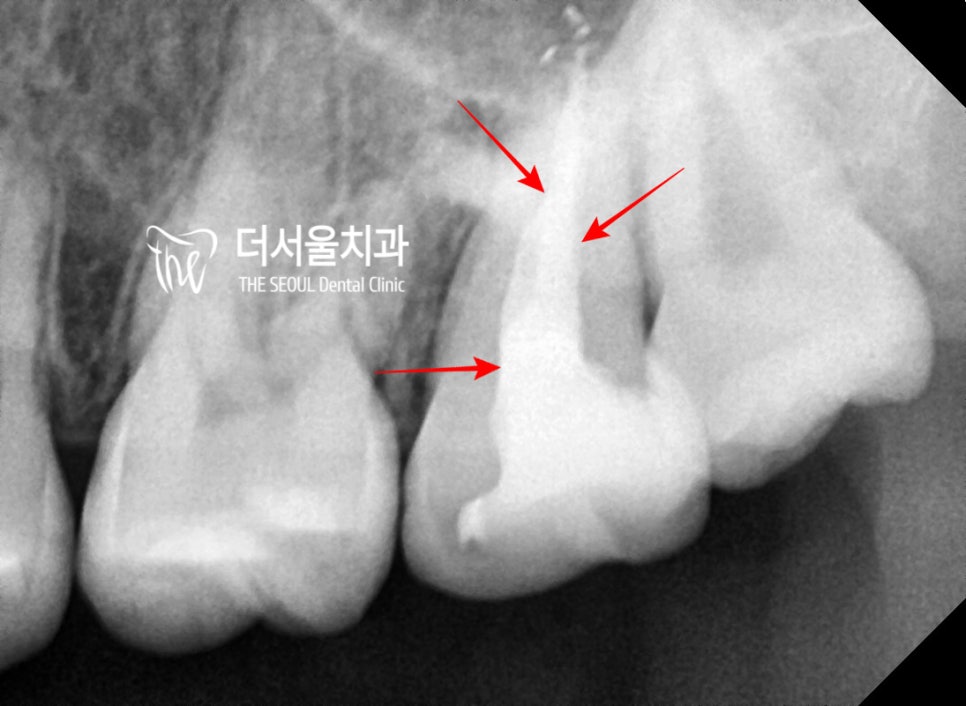

이곳은, 인레이 하방으로 2차 우식이

깊게 형성이 되어서 신경치료까지

진행을 했던 곳입니다.

여기 또한, 충치를 다 제거하니

남은 치질이 거의 없었습니다.

크라운은 올려야 되기 때문에,

부족했던 치질은 코어 작업을

통해서 보강을 했으며

인상 채득을 통해서,

지르코니아 크라운까지 올려드렸습니다.